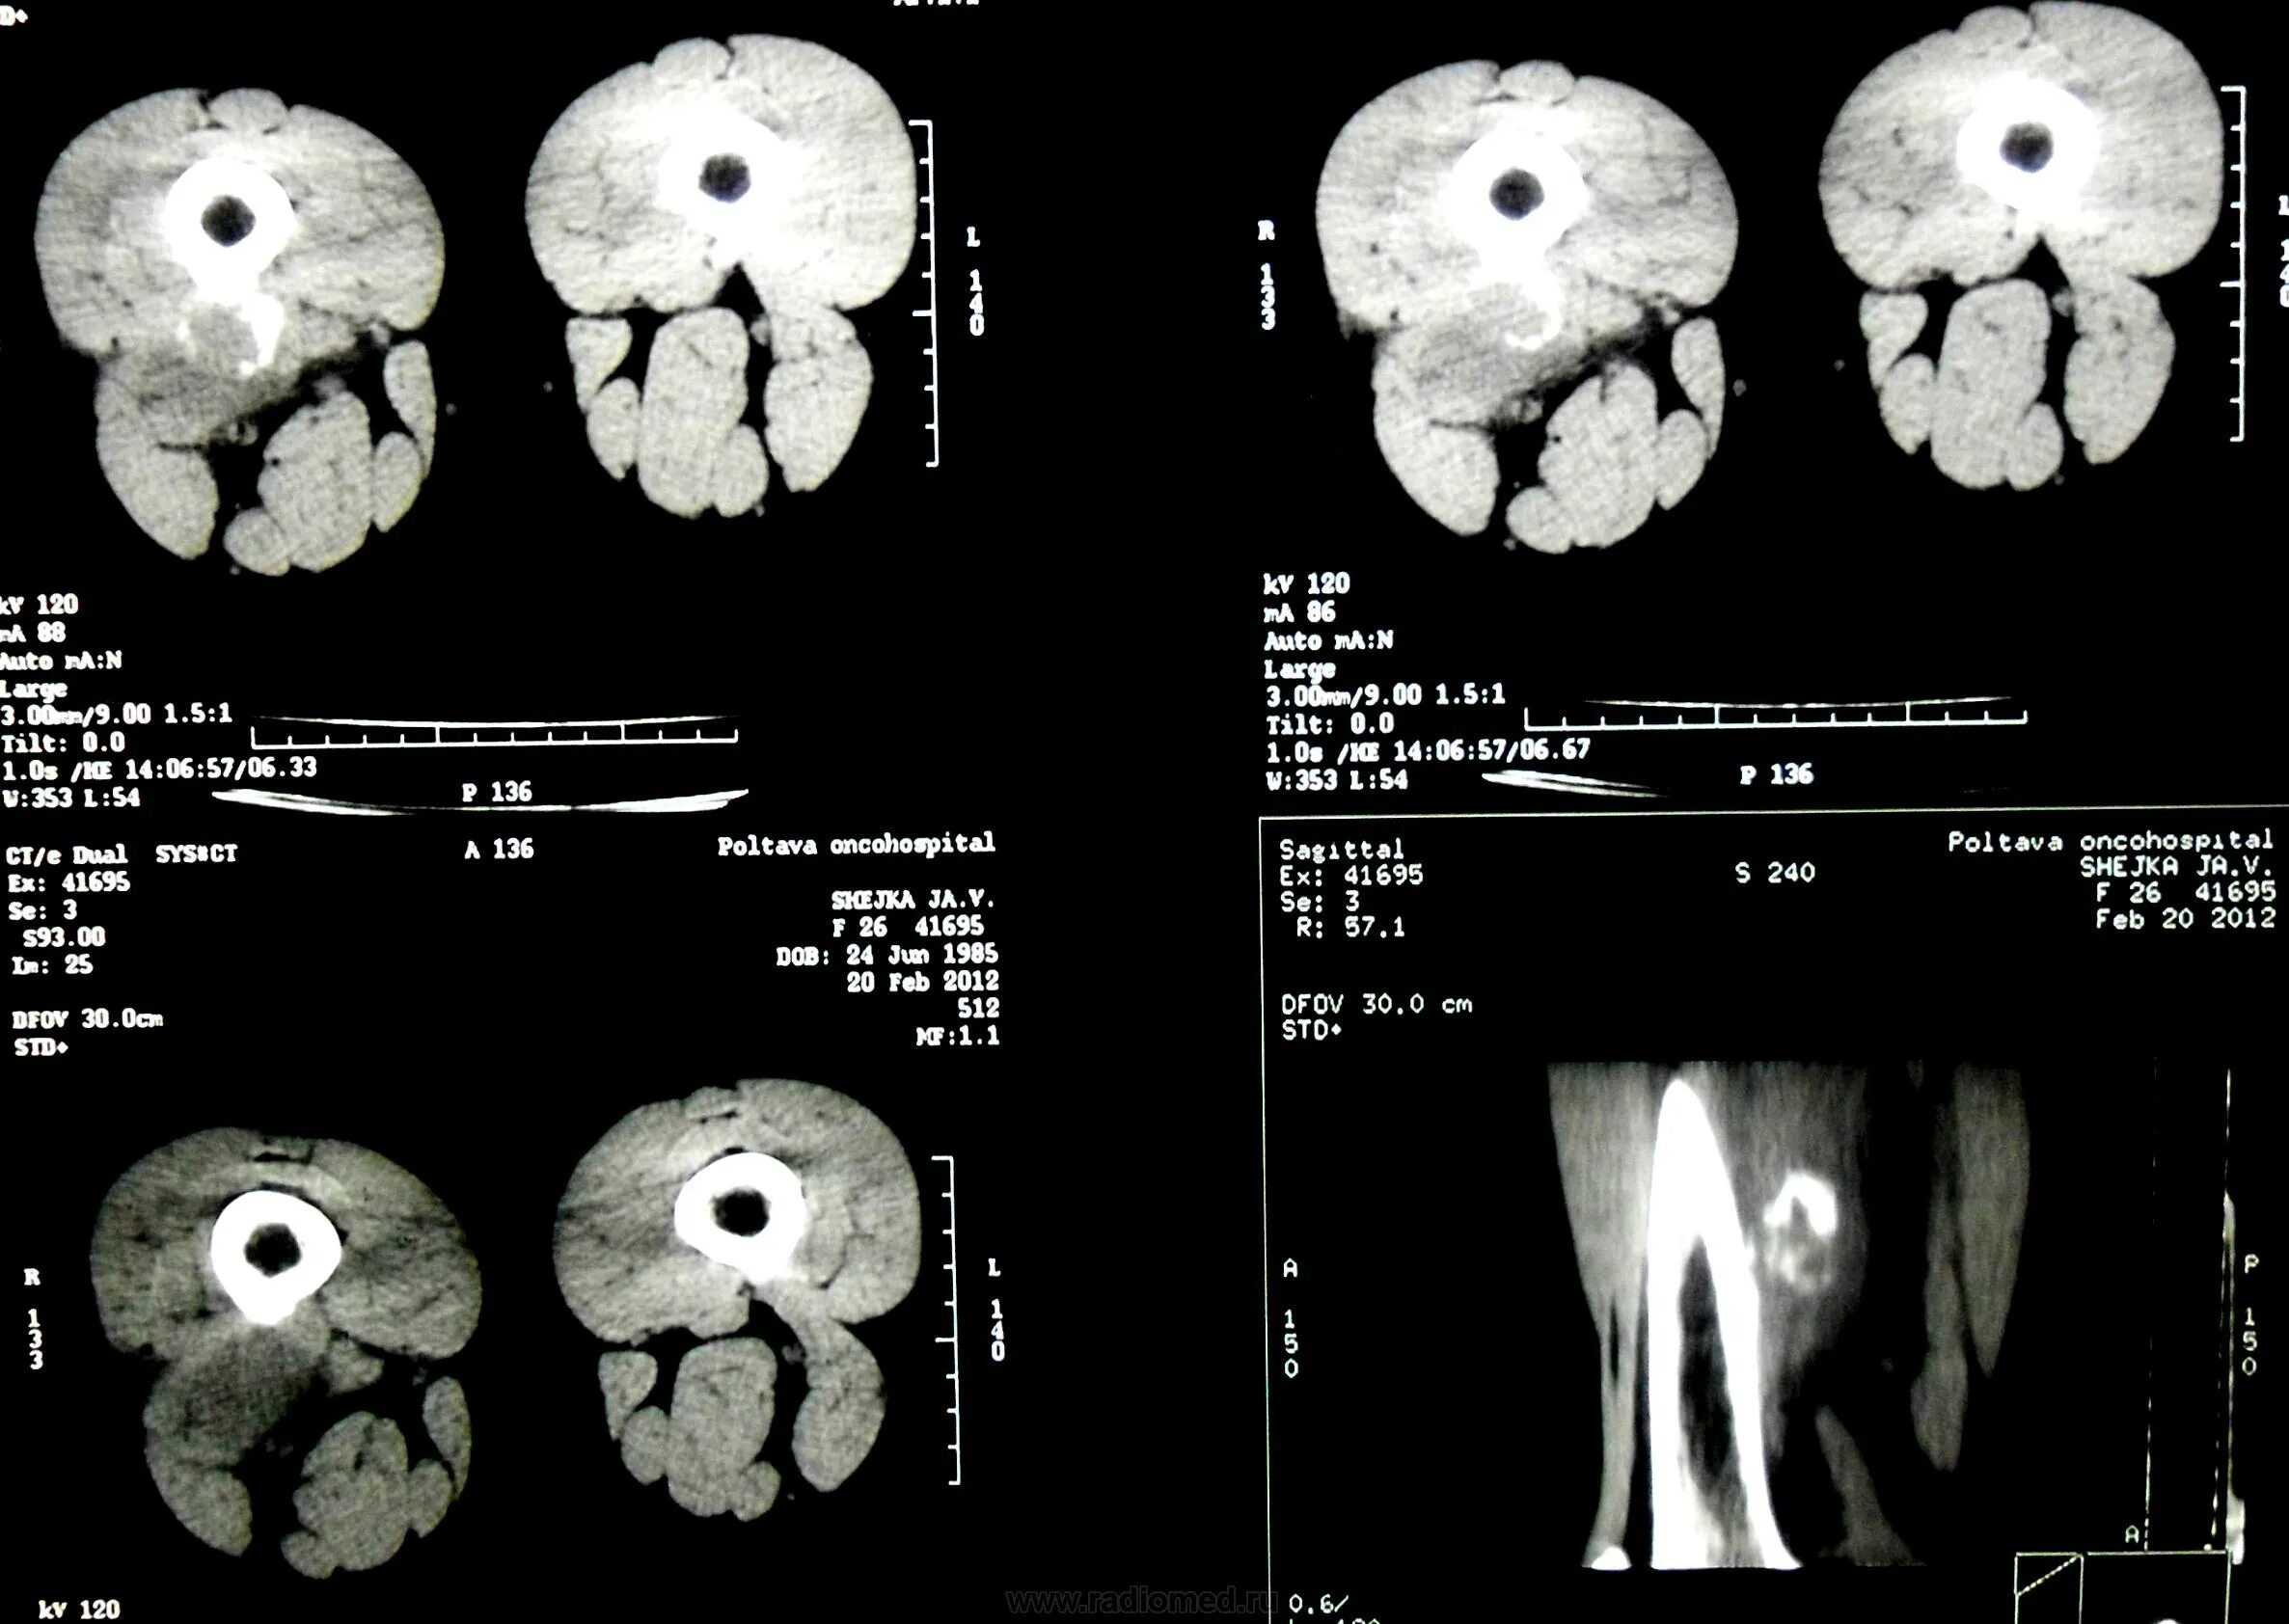

Объем гематомы на кт